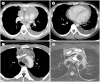

The mediastinum is the most prevalent site of extragonadal teratomas. Patients with mediastinal mature teratomas are usually young adults, and the condition does not show significant sexual differences. Mediastinal teratomas are mostly located in the anterior mediastinum. Patients are usually asymptomatic, although they can have several complications when the teratomas become large or rupture. Most mediastinal teratomas can be diagnosed using CT. Diagnosing ruptured or malignant teratomas is challenging because of their atypical clinical and radiological presentations. In this article, we describe various manifestations of mediastinal teratomas, with an emphasis on radiologic features.